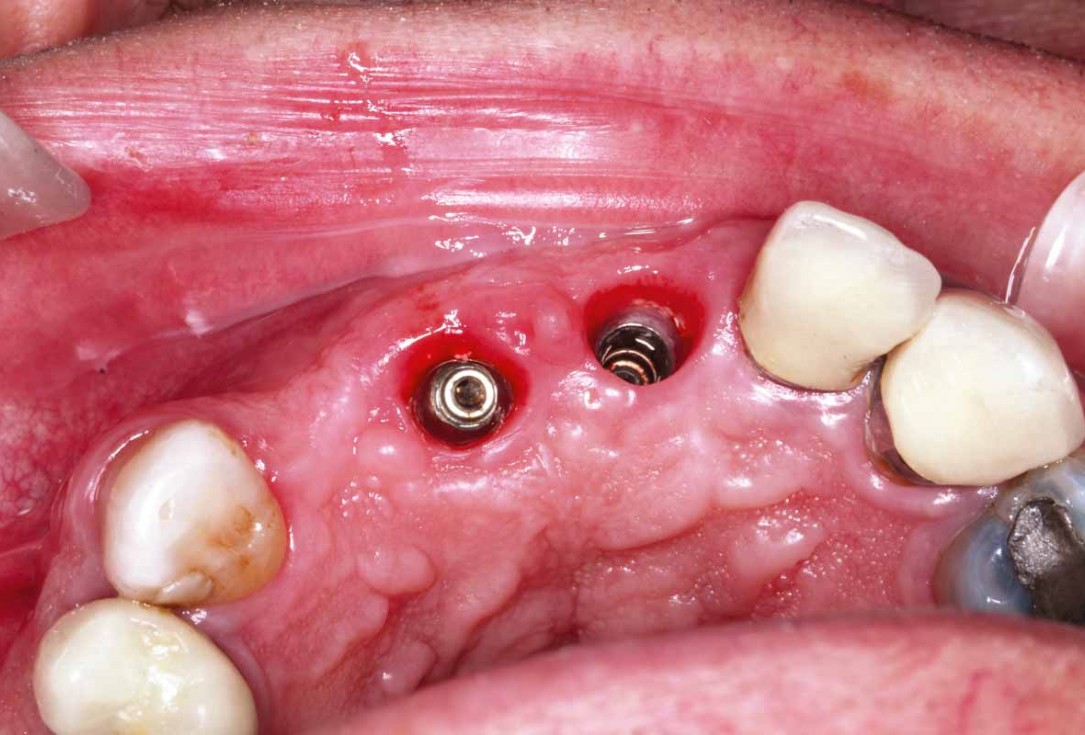

8/27 - Implants #11 and #21: occlusal view

GBR and soft tissue augmentation with cerabone® and mucoderm® - H. Maghaireh & V. Ivancheva